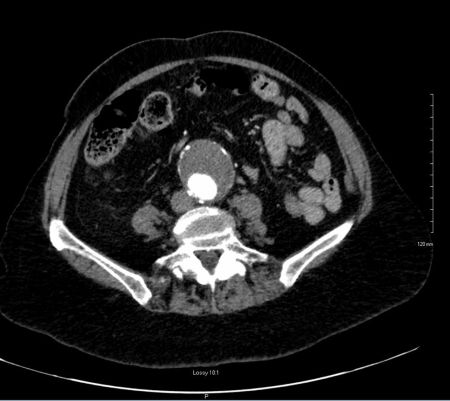

A 75-year-old female with a significant past medical history of hypothyroidism, and allergies to levothyroxine, presented to the emergency department with pain around her shoulder blades and shortness of breath. The patient described the pain as sudden in onset and denied any trauma to the back, heavy lifting, or physical activity. She denied any recent sickness, fevers, chills, chest pain, nausea, or diarrhea. On physical exam the patient appeared in acute distress and uncomfortable due to severe pain but otherwise her physical exam was unremarkable. Patients' vitals demonstrated hypertension, with initial blood pressure of 194/109. POCUS showed large aortic aneurysm (Figure 1). Computed tomographic angiography (CTA) of the chest demonstrated diffuse aortic wall abnormalities with extensive mural thrombus and irregular wall appearance (Figure 2). Areas of high attenuation within the aortic wall suggested the presence of blood products, indicating an acute on chronic process with mural ulceration and likely penetrating atherosclerotic aortic ulcers with blood dissecting into the aortic wall. Additionally, imaging revealed a large infrarenal abdominal aortic aneurysm measuring 5 cm, without evidence of rupture or extravasation. Patient was started on an esmolol drip, admitted to the ICU with consultation by Cardiothoracic surgery and Vascular surgery.

CTA image demonstrating extensive mural thrombus and a 5 cm infrarenal abdominal aortic aneurysm

Figure 2. CTA image demonstrating extensive mural thrombus and a 5 cm infrarenal abdominal aortic aneurysm.